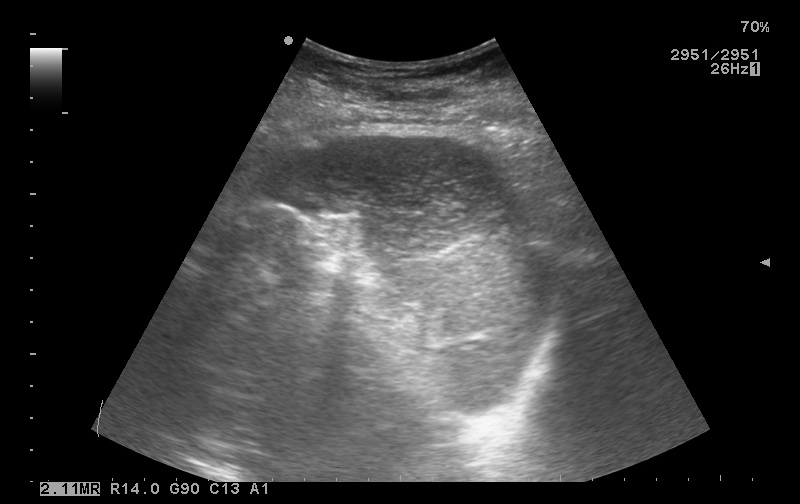

Исследование 2014 года.

Женщина 65 лет, с мерцательной аритмией и сердечной недостаточностью.

Вот такая селезенка.

333_20140320_ABDOMEN_0007.jpg